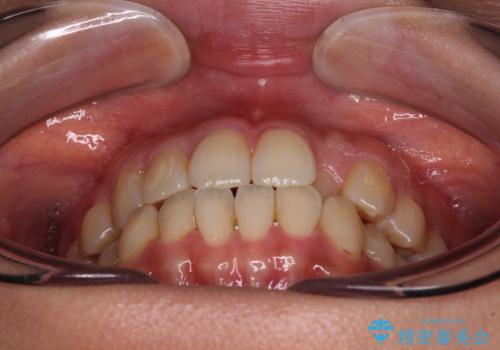

- 前歯のクロスバイトを改善したいとのことで来院された患者様です。

舌の突出癖が認められたため、デコボコ改善に伴い前歯が前突する可能性があったため、舌のトレーニングをしっかりと行うよう指導しながら治療を進めることとしました。

舌のトレーニングをしっかりと行っていただき、補綴治療も含めて1年強の短期間で治療を終えることができました。